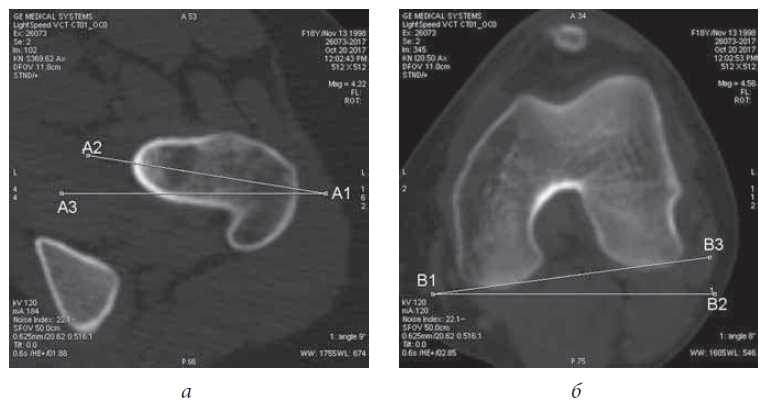

TT–TG Index

Two of the specific sections measured are required for calculation of the TT–TG index: the section in the proximal part of the femoral block, where the intercondylar fossa has the shape of a “Roman arch” and a slight induration is determined on the lateral facet of the femoral block (Fig. 1a), and the section through the proximal part of the tibial tuberosity (Fig. 1b). The distance between the deepest point of the patellar surface of the femur (line A1–A2) and the point at the center of the tibial tuberosity (line B1–B2) are calculated. In our study, the TT–TG index in the control group was less than 15 mm. In four patients with unilateral patellar instability on the contralateral side, the index value was 18 mm. This indicates a predisposition to subluxation and instability of the patella. Patients with a TT–TG index value of more than 20 mm underwent corrective osteotomy of tibial tuberosity in the treatment of patellar instability, and cases with a TT–TG index of 15–20 mm, the patients underwent arthroscopic stabilization of the patella with MPFL grafting. In addition, we noted that the greater the TT–TG index value, the more frequently the dislocations occurred and the signs of instability were more pronounced. However, the severity of the pain syndrome did not depend on this indicator.

Fig. 1. Measurement of the TT-TG index